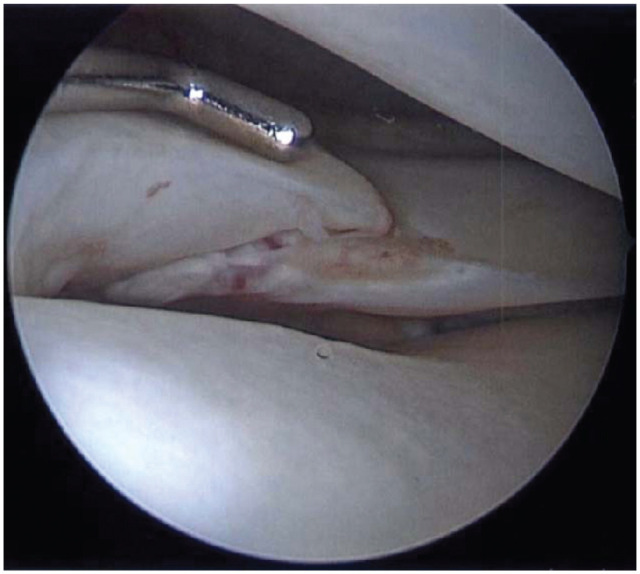

Background: Lateral meniscal oblique radial tears (LMORTs) of the posterior horn typically occur in the setting of an acute anterior cruciate ligament (ACL) rupture. Despite publications pertaining to the prevalence, biomechanics, and surgical repair techniques of LMORTs, studies reporting mid-term outcomes after LMORT repair are lacking.

Methods: A retrospective chart review was conducted on 845 patients who underwent a meniscal repair at The Ohio State University Sports Medicine Center from 2017 to 2019. Operative reports and images were manually reviewed to identify LMORTs occurring concomitantly with ACL rupture. Subsequent knee surgery, meniscal repair failure, and postoperative complications were identified, with failure defined as retear at the same meniscal site. Patients without at least 2 years of follow-up were excluded. Patients were contacted postoperatively for evaluation of patient-reported outcomes (PROs)-including the Knee injury and Osteoarthritis Outcome Score (KOOS), Marx activity rating scale (Marx), and pain on a visual analog scale (VAS).